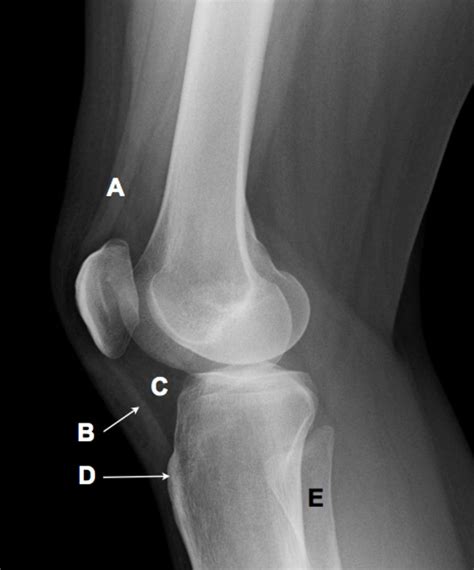

A Lateral Knee Xray is a type of radiographic imaging that captures a side view of the knee joint. This view is essential for evaluating the alignment of the bones, the condition of the joint spaces, and the presence of any abnormalities such as fractures, dislocations, or arthritis. The lateral view complements other views, such as the anteroposterior (AP) and oblique views, to provide a comprehensive assessment of the knee.

Interpreting a Lateral Knee Xray

Interpreting a Lateral Knee Xray requires a trained eye and knowledge of knee anatomy. Here are some key points to look for:

• Bone Alignment: Ensure that the bones are properly aligned. Any deviation can indicate a fracture or dislocation.

• Joint Spaces: Check the joint spaces for any narrowing, which can suggest arthritis or other degenerative conditions.

• Fractures: Look for any breaks or cracks in the bones, which can indicate a fracture.

• Soft Tissue Signs: While not always visible, soft tissue injuries can sometimes be inferred from the presence of joint effusion or other indirect signs.

• lateral knee xray labeled